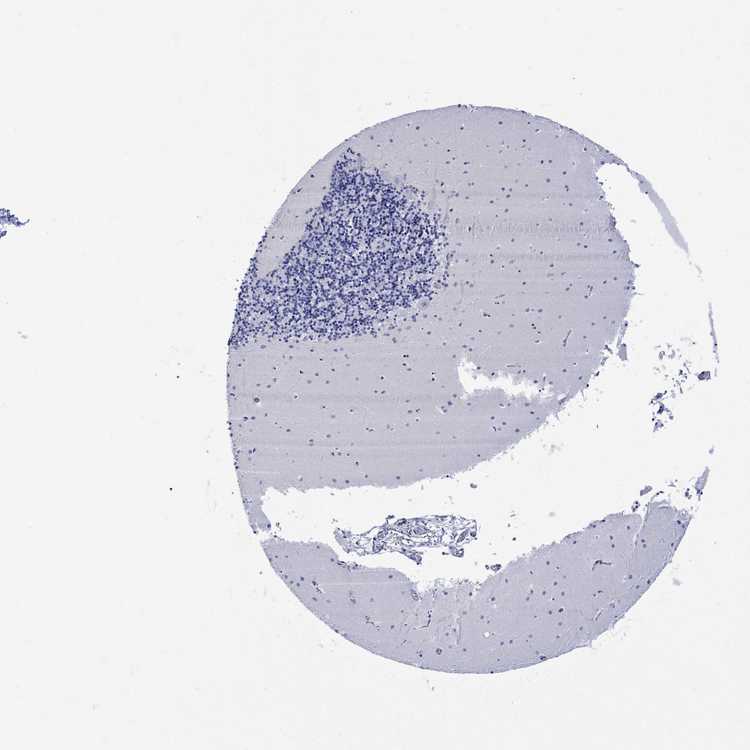

CEREBELLUM - Antibody stainingi

Antibody staining in the annotated cell types in the current human tissue is reported as not detected, low, medium, or high, based on conventional immunohistochemistry profiling in selected tissues. This score is based on the combination of the staining intensity and fraction of stained cells.

Each image is clickable and will lead to virtual microscopy that enables deeper exploration of all samples and also displays staining intensity scores, fraction scores and subcellular localization as well as patient and tissue information for each sample.

Antibody HPA059558

Purkinje cells Not detected

Cells in granular layer Not detected

Cells in molecular layer Not detected